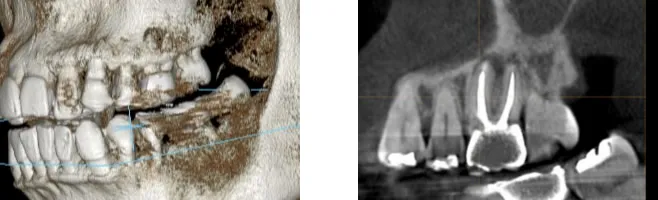

CT断層撮影

自費診療の場合は、レントゲンに加えて、必要に応じてCT断層撮影を行います。CT撮影は、3Dでの画像診断が可能な点や骨や空洞にさえぎられた箇所も、病巣がはっきり映るという点でレントゲンにはできない診断が可能になります。血管や神経の位置、顎の骨の様子、歯の根の数などを立体として映し出すことによって、それらの位置を確実に見極めることができるため、患者様の状態を的確に判断することがでるため、治療が成功する可能性が高くなります。